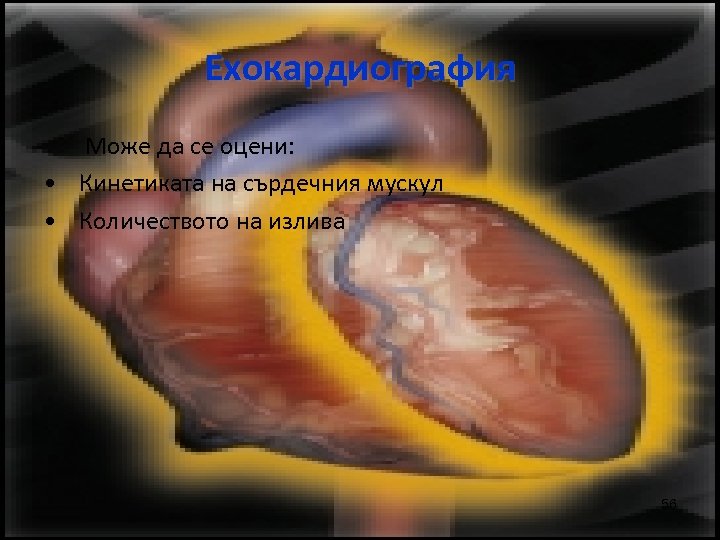

Ехокардиография Може да се оцени: • Кинетиката на сърдечния мускул • Количеството на излива 56